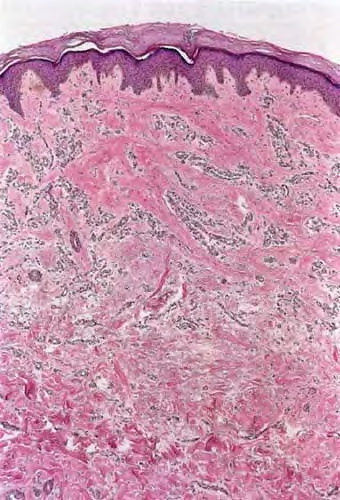

microvenular-hemangioma